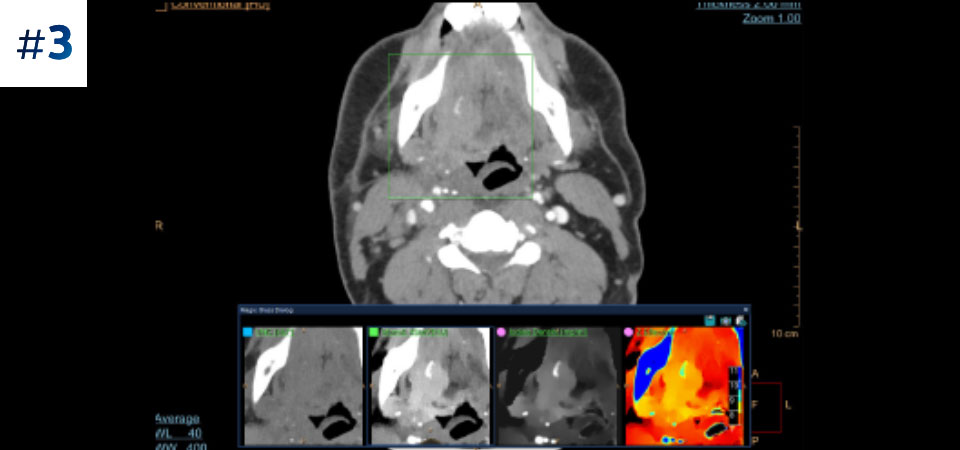

Neck mass

Go beyond conventional CT. See how layers of spectral-detector results can enhance your diagnostic confidence.

See the difference between spectral-detector CT and conventional CT